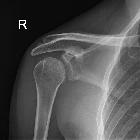

Loss of half-moon overlap sign, which does not really roll off the tongue, is a sign of posterior shoulder dislocation on AP radiographs.

On a normal true anteroposterior image, there is a half-moon overlap between the humeral head and the glenoid. In a posteriorly dislocated shoulder, there is lateral displacement of the humeral head with respect to the glenoid (losing the half-moon overlap).